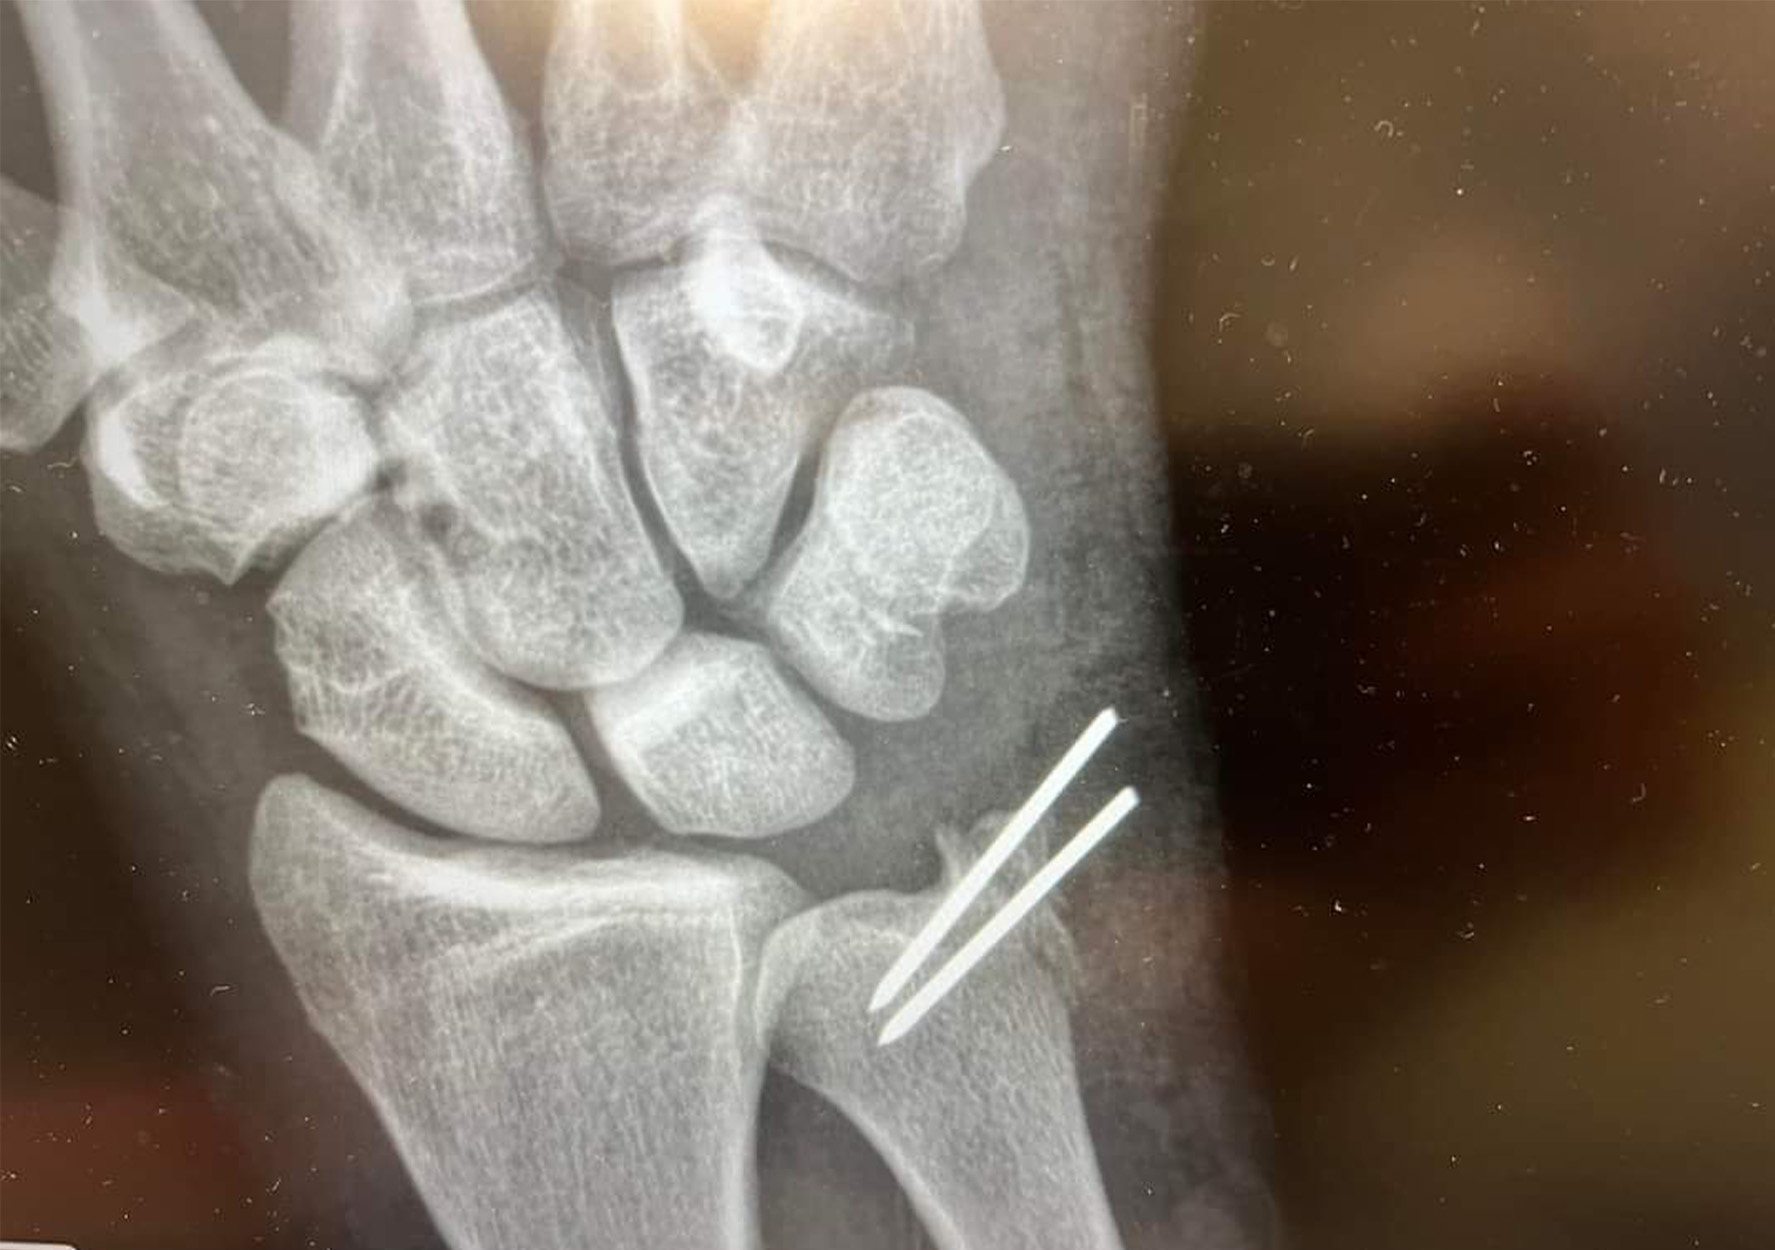

Once on the surface, his dive buddies hurried over and pulled him in the boat. The doctor who was onboard went straight into ER mode, removing Fayard’s glove and wrapping his hand tightly with a towel to stem the bleeding. The boat’s captain used his inReach to contact emergency services, and by the time they were 10 miles out, a Wildlife and Fisheries boat showed up to re-dress Fayard’s hand and escort them into the marina. From there, Fayard was transported to one hospital, and then another, where he underwent surgery to repair the severed tendons in his right hand and wrist.

The doctors told Fayard that he might lose some strength in a couple fingers, but they expect his hand to fully recover. Which, for him, feels incredibly lucky. He says the glove made a huge difference that day, and it was one of several factors that made the attack less bloody than it could have been.